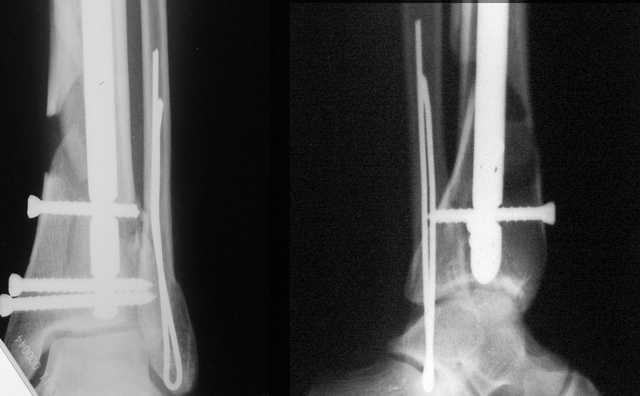

Еще, кстати, о фиксации лодыжки, если уж непременно хочется ее отдельно стабилизировать - при таком характере перелома замечательно должен сработать предложенный проф. Лазаревым с соратниками способ фиксации напряженной V-образной спицей. Опять же, открытая репозиция не нужна, мы делаем непрямую репозицию именно аппаратом. В приложении пример, там перелом малоберцовой куда менее поперечный, чем в данном случае, но все равно получилось закрыто без пластинки.

A propos fibular fixation if one is eager to stabilize it separately. In the fracture pattern a way of closed fixation by V-shaped stressed wire (advanced by colleagues from Moscow, prof. Lazarev A.F. et al.) must be excellent. We use indirect closed reduction by the external fixator. Example attached, that fibular fracture is even more suitable for plating but the wire did the job.